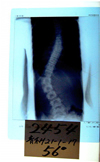

装具装着立位後方写真を見ていただくと一目瞭然です。

この写真は大阪医科大学装具です。

左記の写真の如く(a)は左腰椎湾曲(b)右胸椎湾曲

しかし、装具は大阪医科大方式で同じタイプ。

湾曲が腰椎でも胸椎でも同じ装具であり

Wカーブでも同じ装具です。

この装具装着姿を見ていただければわかるように左腰椎湾曲、右胸椎湾曲でも同じ装具である、

しかも、パッドがないこのタイプの欠点を述べますと下記の通りです。

(a)は左腰椎湾曲にこの装具は装着時よくても身長が伸びると脊柱が伸びるが、

装具本体の形は変わらないため初期に作成した装具の位置では圧迫が弱くなる。

そのため左腰椎の進行と左肋骨下部が盛り上がる。(パッドのない装具のため初装着でも効果は少ない)

(b)右胸椎湾曲にこの装具は効果がない。右胸椎湾曲の極点に装具本体が届いておらず、

身長が伸びることにより押さえる効果がない。(写真の通りパッドがなく効果ない)